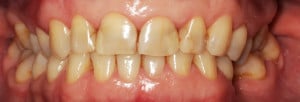

Do kliniki Stomatologia Bez Bólu zgłosiła się pacjentka, lat 61 z problemem nadwrażliwości zębów. Po przeprowadzonym wywiadzie stwierdzono spożywanie sporej ilości sezonowych owoców (truskawki, wiśnie, czereśnie, czarna porzeczka), nawet 3 razy dziennie. Następnie wykonano badanie wewnątrzustne. Stwierdzono obecność płytki nazębnej, ciemnego osadu oraz kamienia nazębnego na części trzonowców: